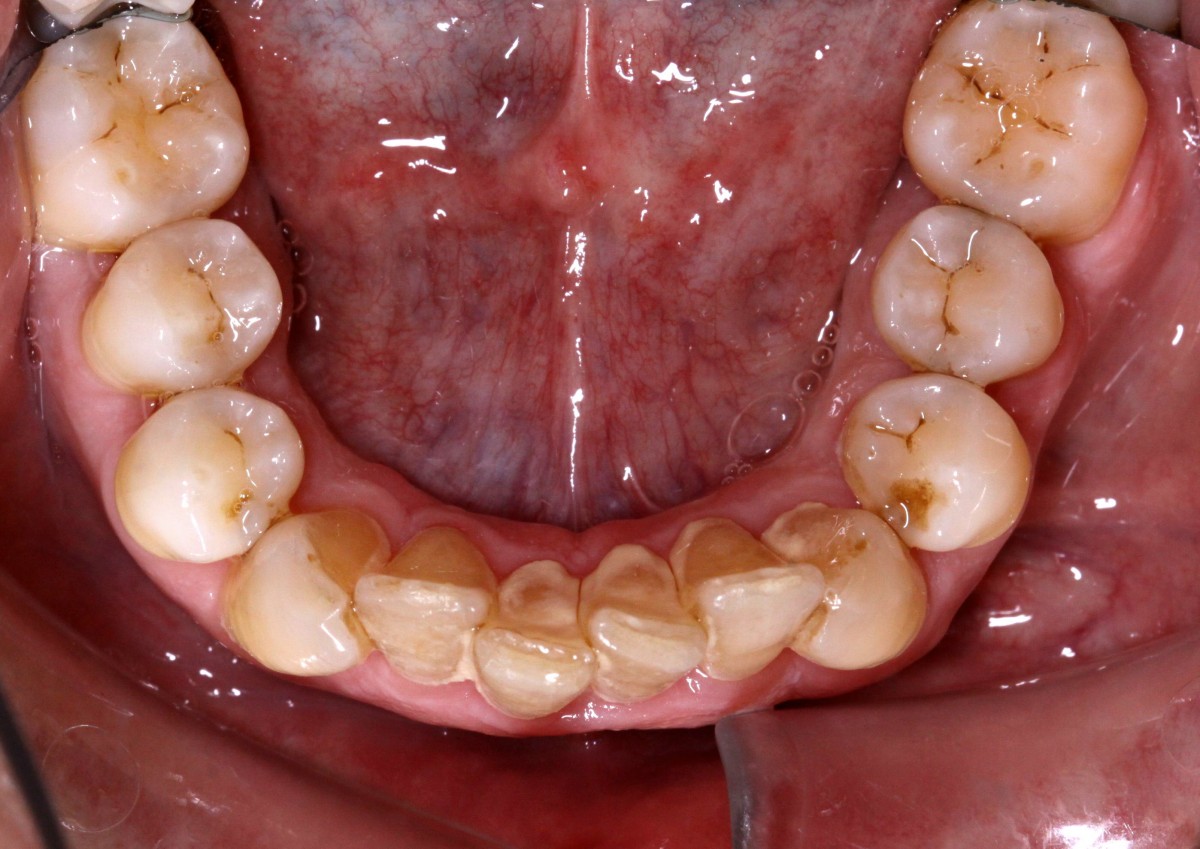

Lower incisors erupted verti- cally and created 2 planes of occlusion and exaggerated curve of spee in the lower arch. The upper lip “pushed” the an- terior incisors lingually and consequently the bite was deepened. Oral hygiene is poor mainly due to the crowding of the lower incisors. The upper diastema resulted in the loss of the interdental papilla between the central incisors (figs. 5, 6).

with extraction of upper first premolars (#14, #24). Space between #11-#21 is slowly opened during the years and space start to develop distally to the upper lateral incisors. Lower incisors are hitting traumatically the palate creat- ing proliferation of the epithe- lium and constant inflamma- tion. Lower anterior crowding is around 4.5 mm (#33-#43) (figs. 7, 8).